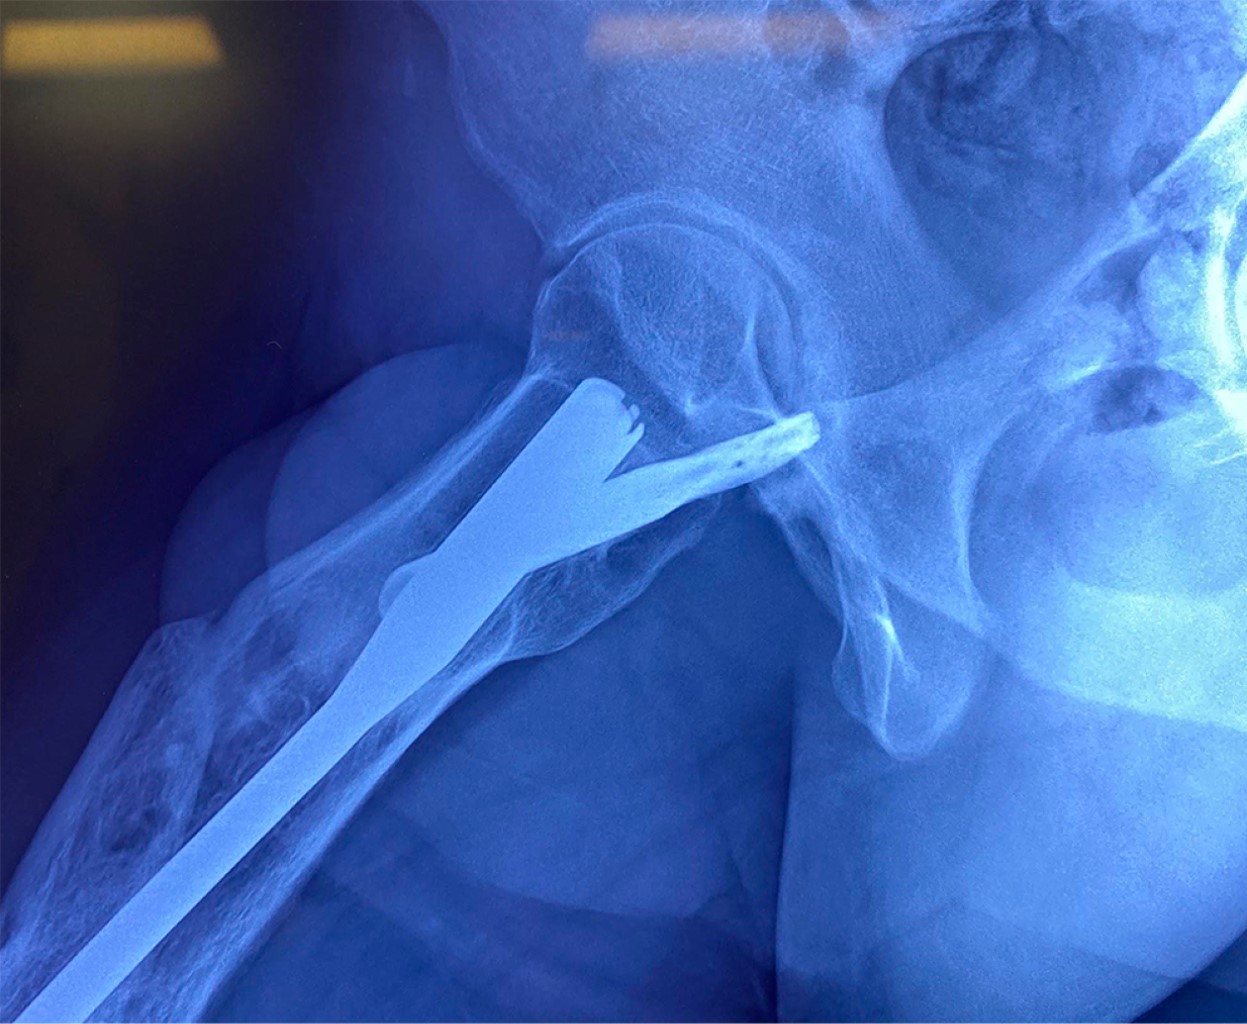

Las radiografías de cadera derecha en proyección anteroposterior (Figura 1) y lateral (Figura 2), así como radiografías de eje mecánico (Figura 3), evidenciando fractura consolidada de fémur diafisario derecho, acortamiento de 2.04 cm de miembro pélvico derecho a expensas de fémur y clavo centromedular anterógrado de entrada trocantérica. La radiografía lateral de cadera derecha revela protrusión posterior de la hélice del clavo centromedular a través de la cabeza femoral encontrándose en contacto con pared acetabular posterior. Este contacto condiciona erosión de pared acetabular alrededor de la protrusión.

Figura 1

Figura 2